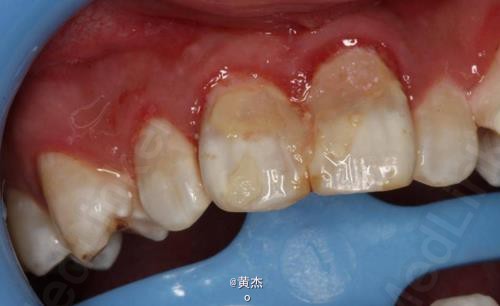

男,刘××,16岁。主诉:11、21牙齿疼痛一周。病史:一周前患者自觉前牙疼痛难忍,未做任何处理。遂来我院牙体牙髓科治疗。牙体牙髓科检查:11、12松动Ⅱº,21松动Ⅰ°。11、21叩诊+++。

诊断:11、21根尖周炎。处理:11、21开髓无活力,大量血性渗出,根管无法测量。于是转诊口腔外科。术前和患者签知情同意书。给患者讲明外科手术有可能失败,最终拔除11、12、21的可能性。口腔外科处理:拔除13.。发现 11牙根几乎完全吸收、21唇侧牙根也被13牙冠压迫吸收到根中1/3。于是术中行11、21MTA根尖区封闭。12暂不做处理,观察半年后考虑进一步治疗方案。